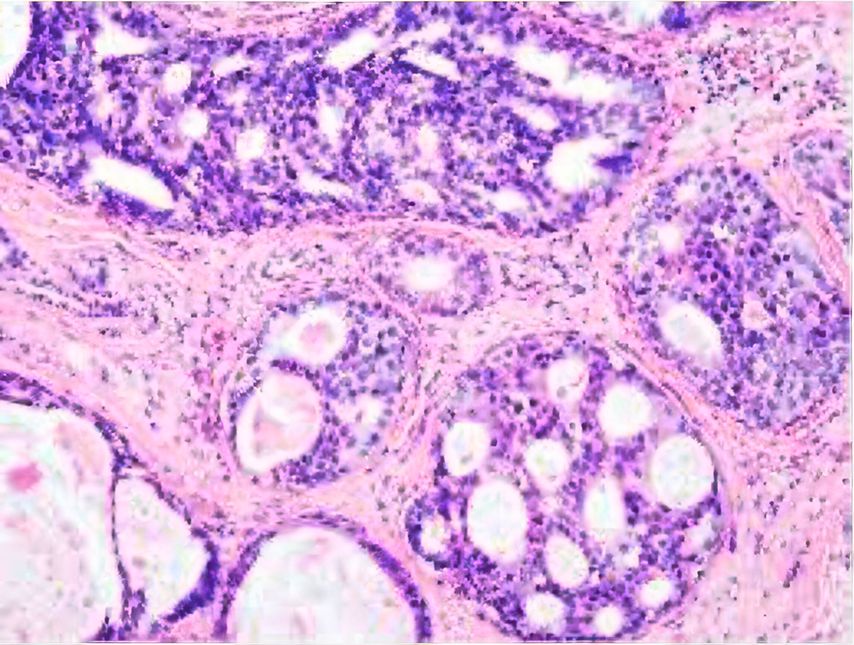

Das duktale Carcinoma in situ (DCIS) beschreibt eine Vorstufe des Mammakarzinoms, bei der maligne Zellen innerhalb der Milchgänge wachsen, jedoch die Basalmembran noch nicht durchbrochen haben (Abb.1). DCIS gilt als nicht zwingender, aber möglicher Vorläufer eines invasiven Karzinoms.1 Daher bestand die Standardtherapie bisher meist aus operativer Entfernung, adjuvanter Radiotherapie und – bei Hormonrezeptorpositivität – endokriner Therapie, in Analogie zum invasiven Mammakarzinom. Mit verbesserter Bildgebung wie Tomosynthese-Mammografie, Früherkennungsprogrammen und zunehmender Durchführung von Magnet- Resonanz-Imaging (MRI) werden heute vermehrt kleine, niedriggradige DCIS-Läsionen entdeckt.2 Studien zeigen jedoch, dass nicht jedes DCIS fortschreitet, und bei operativer Entfernung findet sich nur bei etwa 10–23% ein invasives Karzinom.3 Zudem führte der Anstieg an DCIS-Diagnosen nicht zu einem signifikanten Rückgang der Zahl an invasiven Karzinomen oder der Brustkrebssterblichkeit. Dies wirft die Frage nach einer möglichen Übertherapie auf.4

Abb. 1: DCIS, H&E-Färbung. Bild mit freundlicher Genehmigung von Prof. Varga